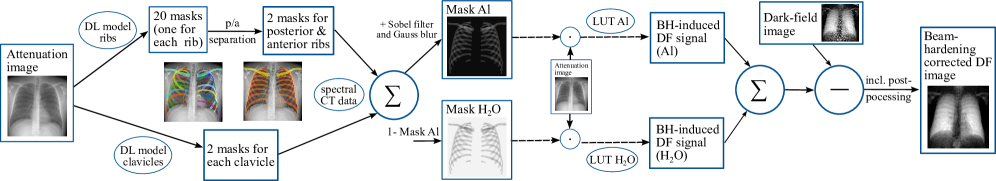

In the approach proposed here, this global weighting factor and the bias-correction term are replaced with a spatially resolved weighting derived from attenuation contribution masks described above in combination with the deep learning-based bone segmentation. Specifically, the aluminum and water masks are used to compute a pixel-wise weighted sum of the LUT-based beam hardening-induced dark-field signals. The resulting correction map is then subtracted from the raw dark-field image to obtain the corrected image. Fig. 2 summarizes the complete pipeline, including segmentation of ribs and clavicles, p.-a. separation, mask generation using spectral CT-based attenuation contributions, and the final BHC implementation using pixel-wise LUT interpolation and subtraction.